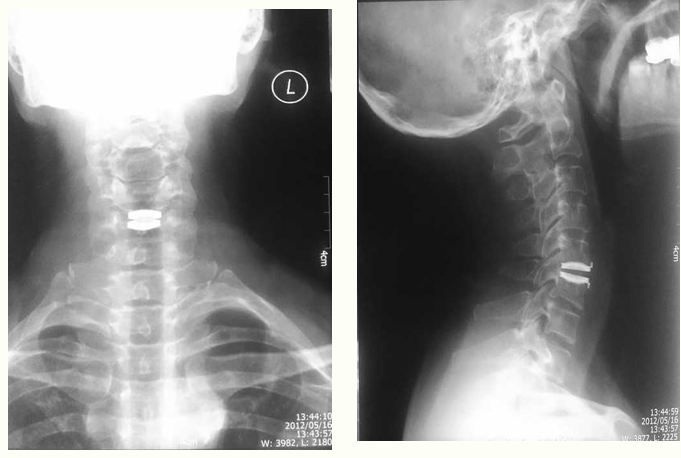

病例一、

彭XX 男性 43岁

主 诉:外伤致双上肢疼痛、麻木4小时专科情况:双侧前臂桡侧肘横纹以下皮肤浅感觉略减退,痛觉过敏,温觉减退。双侧指屈肌、指伸肌、骨间肌肌力均为2级,双侧腕屈肌肌力为3级,双侧腕伸肌肌力4级,肱二头肌、肱三头肌腱反射(+++),跟膝腱反射(+++),双侧Hoffman sign (-),Babinski sign(-)。

JOA评分:9分。

影像学检查